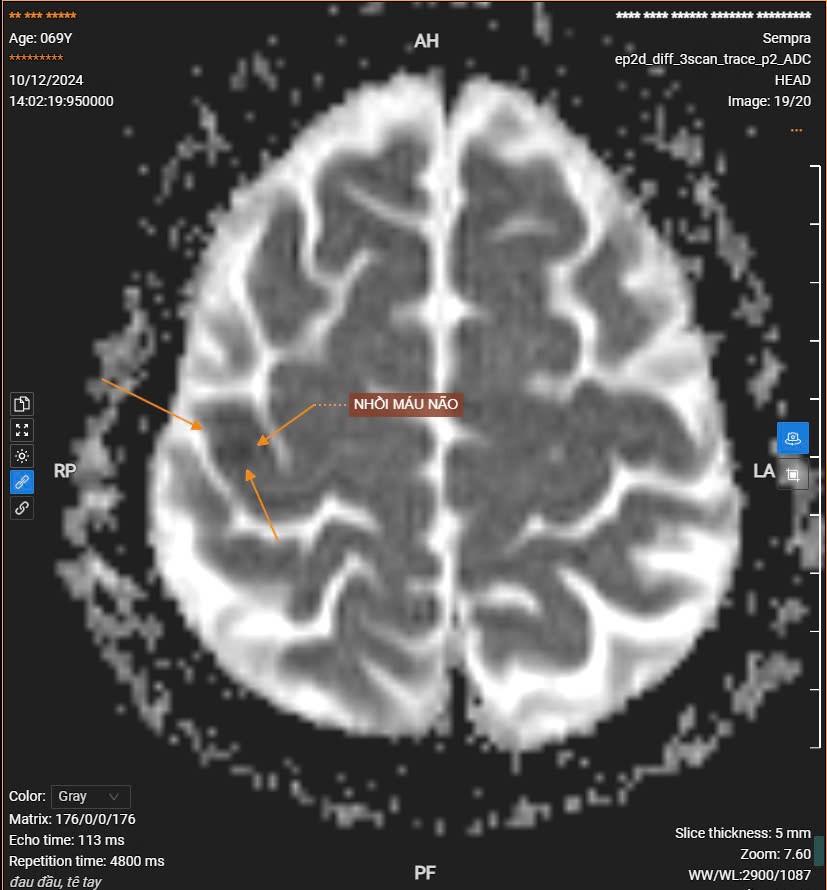

Dưới đây là một số hình ảnh chụp MRI sọ não cho bệnh nhân gặp các vấn đề: đau đầu, tê tay, tê môi, liệt nửa người, ... khi thăm khám tại BVTB trong những ngày qua.

Bn nam 69 tuổi đến khám vì đau đầu, tê nửa người trái kết quả chụp MRI sọ não phát hiện hình ảnh vài ổ nhồi máu não cấp tính nhỏ thùy trán đỉnh phải.